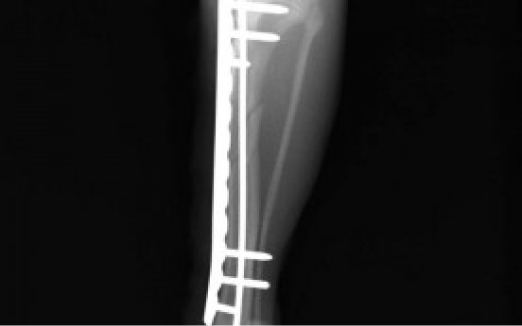

整形外科

整形外科とは、骨や関節などに発生した異常(骨折や脱臼など)を手術によって治療するものです。

現在対応している疾患は、四肢骨折整復手術(前足、後ろ足の骨折整復)、膝蓋骨内方脱臼に対する安定化手術、前十字靭帯断裂に対する安定化手術(関節外法)、胸腰部椎間板ヘルニアに対する減圧手術(へミラミネクトミー)などです。